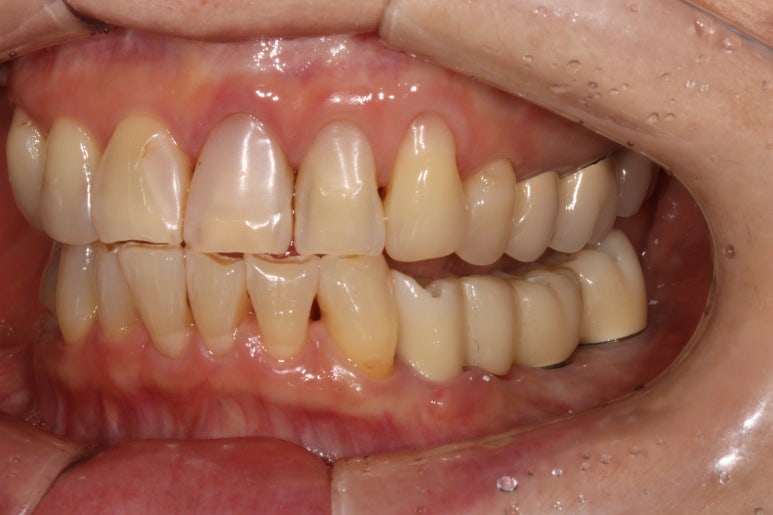

저희 병원에 작년에 오셨던 여자환자분입니다.

왼쪽 아래 어금니가 2개가 없으신 것을 아실 수 있으실텐데,

그 자리에 편측 틀니를 쓰고 계셨고, 너무너무 불편하여 임플란트로 치료 받으러 내원하셨습니다.

왼쪽 아래 큰어금니 두개가 없었고,

교합면 사진을 보시면, 앞의 두 치아에 surveyed crown (서베이드 크라운)을 설치하고 부분 틀니를 사용하게 하심을 단번에 알 수 있었습니다.

중요한 것은 해당 부위의 대구치 두 개를 뽑은지가 너무 오래되셨고, 틀니를 사용하셔서

대부분의 부착치은 (각화치은)이 사라져 있는 상태였습니다.

그래서 유리치은 이식술을 강하게 권유드렸고, 환자분이 다행히도 필요성을 이해해주셨어요.